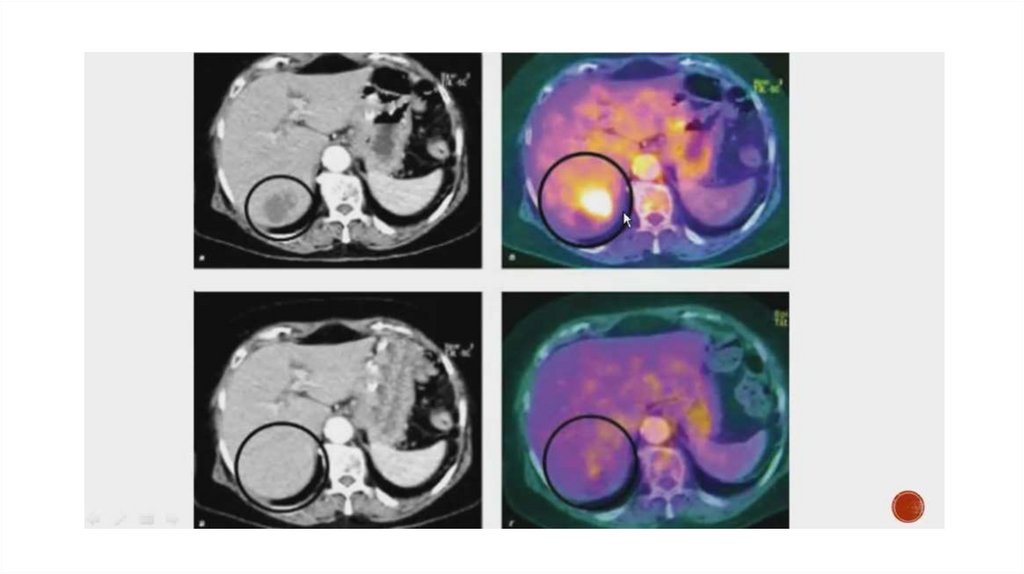

После узи мрт можно делать только после 11.5 мес. (поэтому лучше до сделать)